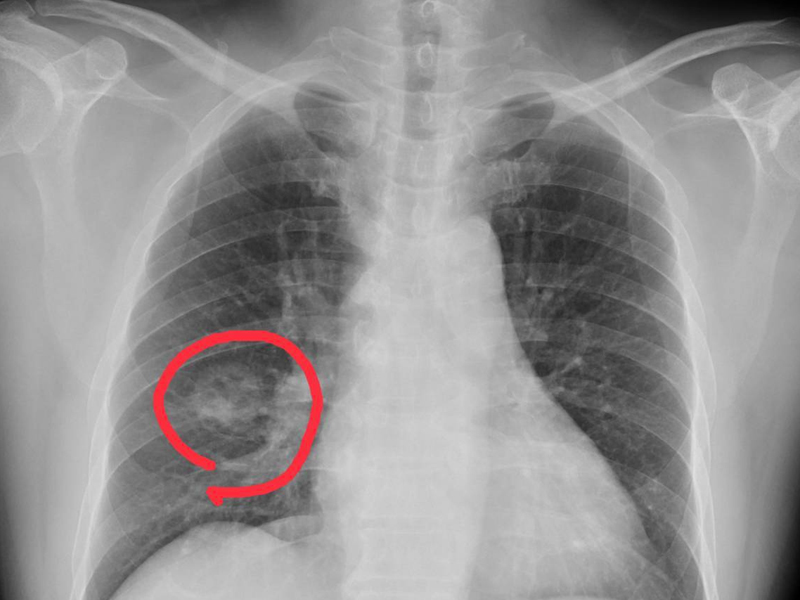

![]() 瀏覽:13643 有種腰痛是癌症的先兆,很多人發現就是晚期 | ![]() 瀏覽:2772 曾經有個廚師,上完廁所不洗手,結果導致 ... | ![]() 瀏覽:428 拜登確診前列腺癌,為何每年體檢未早發現? |